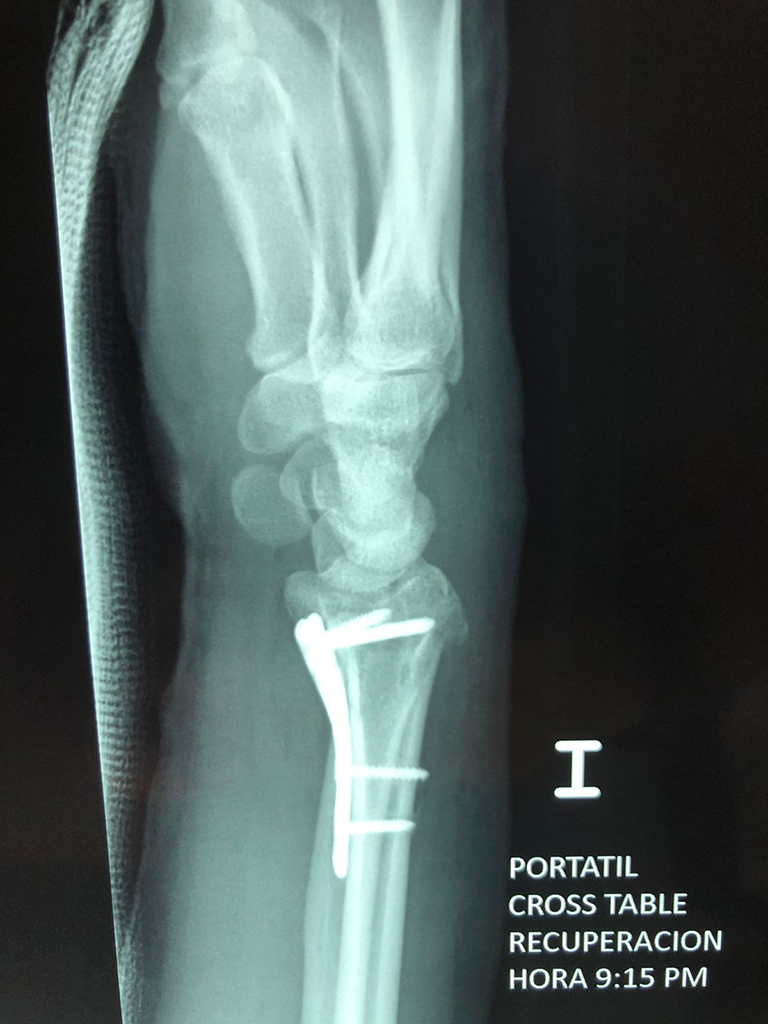

Cirugías de Codo - Cirugías de Muñecas y Manos

Los procedimientos más comunes en cirugía de la mano son aquellos destinados a reparar traumatismos, incluyendo lesiones de tendones, nervios, vasos sanguíneos, y articulaciones; huesos fracturados; y quemaduras, cortes, y otros daños de la piel.